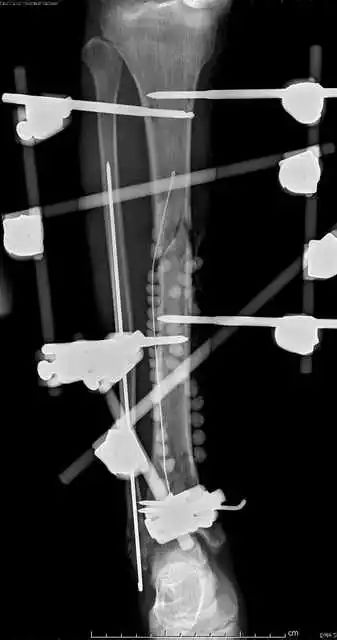

最后一个病例

(网友提供)最后的病例是伤后40天由外地转来。开放骨折外固定架固定,骨坏死外露,用连珠和双氧水冲洗。入院时还存在足下垂,腓神经损伤、胫后动脉损伤。

Tips

• 接收该患者后第一次手术  清除病灶去除死骨27cm

• 抗生素骨水泥填塞。远端整块水泥包裹外露骨质,近端连珠以便骨搬移

• 钢丝克氏针张力牵拉皮肤,缩小创面

• 5天后下地部分负重走路

• 联合骨牵引纠正足下垂,5天后足下垂纠正后去除跟骨骨牵引针,保留胫跖骨牵引维持足于功能位。

• 而后行骨搬移、半开放植骨(如下)

• 第一次的骨水泥于80天后去除,行半开放植骨(植骨表面覆盖抗生素骨水泥)

• 因为有皮肤缺损,用骨水泥做成瓦片闭合伤口=半开放植骨

• 自体优质松质骨(如图)

• 皮肤采用了钢丝牵张闭合

• 骨搬移+半开放植骨=治疗缺损

• 植骨后一个月去除瓦片骨水泥,创面新鲜

• 钢丝克氏针张力闭合伤口加游离植皮

• 继续骨搬移

• 修整

• 入院6个月腓总神经恢复,胫前动脉再通

• 总的治疗过程2年基本完全康复

1、双氧水不要用于急症手术冲洗伤口,也不要用于换药2、应用骨水泥时做骨搬移有阻挡作用3、骨搬移过程中,持续的外伤刺激修复中血管扩张增生,原来闭塞的血管再通或周围的动脉扩张。4、单边外固定架加半环架搬移基  本不影响关节活动5、皮肤牵张法的基本使用方法是 皮内置入细克氏针后钢丝缝合。欢迎指正,谢谢大家。